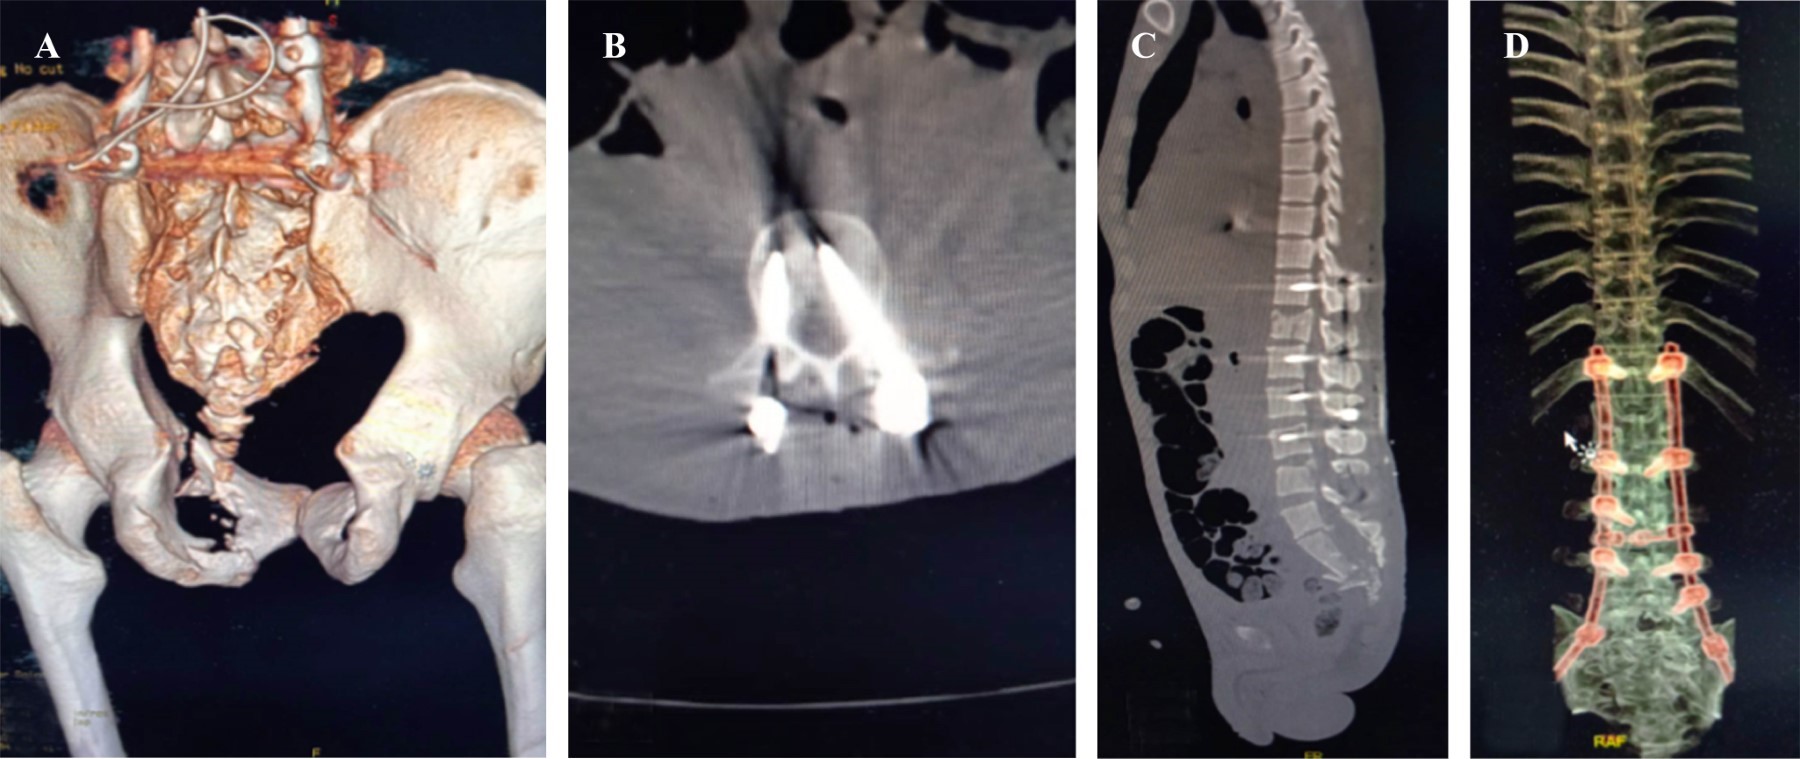

Se realizan radiografías de control serie pélvica y radiografías de codo y columna (Figura 2). En estas series se evidencian disrupción del anillo pélvico anterior del lado izquierdo, fractura articular de húmero, con fractura en arcos costales cinco y seis; serie radiográfica de Judet. Posteriormente se realizan tomografía axial computarizada (TAC) con cortes axiales sagitales y coronales de columna con pelvis (Figura 3) y reconstrucción 3D (Figura 4) donde se observa fractura del anillo pélvico tipo C de Tile por mecanismo de cizallamiento vertical en donde se observan fracturas de rama iliopubiana en zona III de Nakatani e isquiática ipsilateral izquierdas con fractura multifragmentada de sacro con patrón H asociada a hundimiento de plataforma de S1 y fracturas transforaminales bilaterales que se unen a nivel de S2-S3 clasificada como C3 por AO. Se encuentran también fracturas de los cuerpos vertebrales que fueron clasificadas acorde con la propuesta de AO, L1 por compresión tipo A4, fractura de L5 por distracción tipo B2 además de fracturas de las apófisis transversas de L4, L3 y L2 secundarias al cizallamiento vertical tipo A0.

El paciente es estabilizado y se ingresa a la unidad de ortopedia para la realización de manejo quirúrgico definitivo. Se realiza para la columna y pelvis una planificación preoperatoria tridimensional con ayuda de realidad virtual (Figura 5), en donde se decide por la pérdida de capacidad de carga de la columna lumbar y su limitación de transmisión de cargas hacia la pelvis, realizar con un abordaje posterior en línea media de región de columna, una instrumentación posterior espinopélvica larga con colocación de tornillos transpediculares bilaterales en T12, L2 y L4; así como instrumentación de pedículo derecho en L5 y pedículo izquierdo en L3, además de instrumentación de ilíaco bilateral con tornillos en corredor LC2, con barras laterales y dando distracción entre T12 y L1 y entre L5 e ilíacos, se coloca además un crosslink para incrementar la rigidez del constructo de nuestra instrumentación espinopélvica larga. Además, se procede en el mismo tiempo quirúrgico una reducción abierta y directa con osteotomía del olécranon tipo Chevron y fijación interna del húmero distal bajo principio biomecánico de sostén con doble placa de reconstrucción en configuración medial y lateral con placas paralelas (Figura 6). En el postquirúrgico inmediato se realiza tomografía con supresión de metales y reconstrucción 3D para valorar adecuada posición de los tornillos transpediculares (Figura 7).